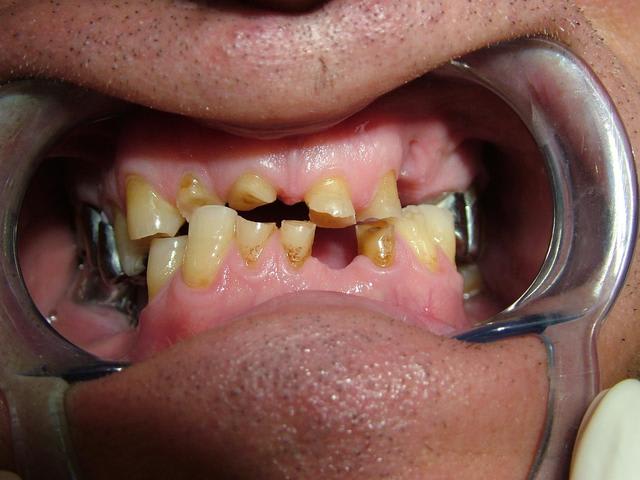

Homme de 57 ans avec DV effondrée.

Contrairement à ce qui a été dit...Il n'y a pas de perte de Dimension verticale. Les secteurs posterieurs sont plus ou moins preservés

Par contre dans le secteur anterieur l'usure des dents à été compensé par une egression qui donne l'illusion de perte de DV...

Le traitement est complexe car on peut pas vraiment augmenter la DV...il y pas ou peu de perte. Si on surevalue la DV, ça peut etre super mal toléré.

Oui...egressé et usée. Regarde l'os alveolaire de la pano.

De toute façon il n'y a pas perte de DV si il n'y a pas perte de calage posterieur...

Je confirme il y a un calage posterieur...presque pas de perte de DV. Donc la distance "maxillo-mandibulaire" n'a pas diminuée.

la mise en occluseur me parait erronée avec ce type d'abrasions les incisives devraient être en contact, mais pas grave l'essentiel c'est l'aperçu. ,

Merci pour toutes les réponses qui m'ont aidé à réfléchir au cas et surtout ne pas me précipiter sur mon plan de traitement stupidement. J'ai revu le patient il y a qq jours et je devais ce jour là lui faire la présentation du plan de traitement. Je lui ai expliqué que son cas était tellment complexe que je n'avais pas pour le moment de solution thérapeutique valable car je n'avais pas encore traité ce type de cas. Le patient a fort bien compris et j'en ai profité pour prendre des radios buccales ; en effet la mise sur occluseur que j'avais sur les précédentes photos était fausse. Le patient "occluse" différement. Voir les nouvelles photos jointes. Il y a très peu de contact antérieur ; j'ai bien demandé une dizaine de fois au patient de se mettre en occlusion pour arriver au même résultat que l'on voit sur les photos. Le patient a bien sur du mal à avoir un occlusion stable.

Ce qui m'interroge le plus c'est comment ce patient est arriver à user le bloc antérieur et arriver à cette situation. Il n'a pas d'habitudes nocives ( ex fumeur de pipes ou autres tics).

Il est vrai que la DV me semble conservé car il y a un calage postérieur côté droit et côté gauche.

Pour l'instant je serai plutôt d'avis de lui remonter de 1 à 2 mm la DV avec une plaque de surélévation ( plaque pendant 2 à 3 mois) pour voir si les ATM supportent et faire des élongations coronaires sur les dents antérieures que l'on conservera.